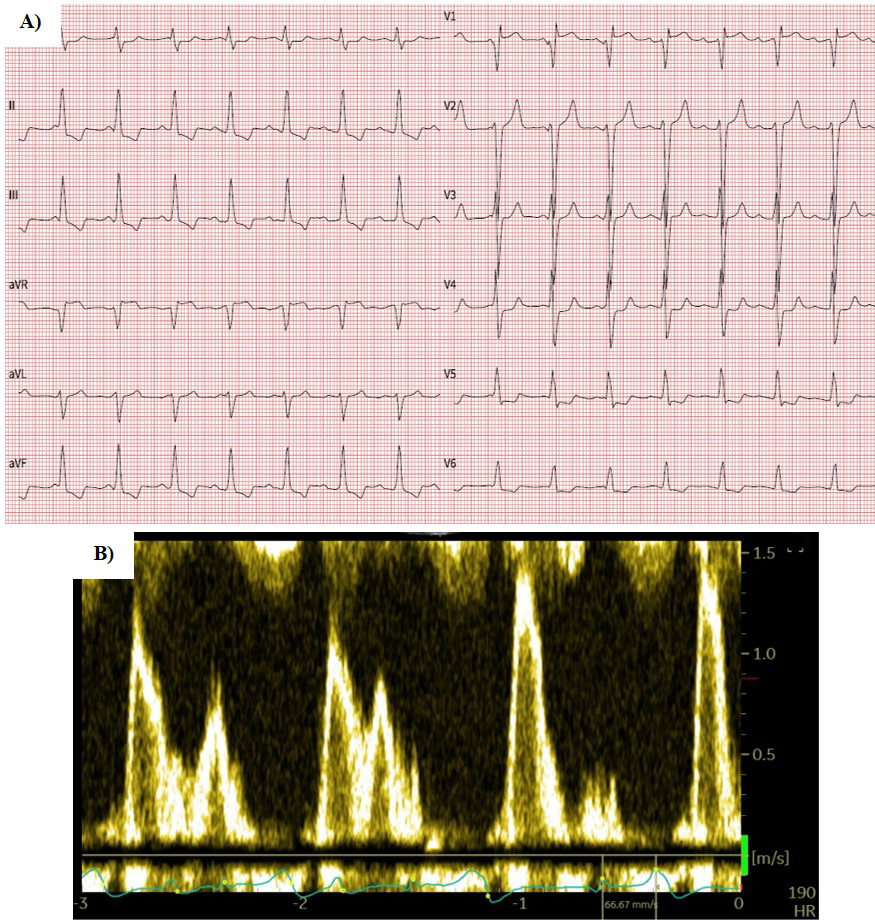

While there were no significant differences in baseline LVEF (p = 1), LVEDVi (p = 0.214), and indexed LV systolic volume (LVESVi) (p = 0.311), baseline LAVI was, as previously described, significantly smaller in patients who converted to SR (p = 0.002) (Table 4). At follow-up, LAVI did not change in any group. The increase in LVEF was numerically comparable in both groups, although, in the SR group, it did not reach statistical significance due to the smaller sample size. Similarly, LVESVi decreased in both groups; however, in the SR group, the decrease did not reach statistical significance due to both smaller sample size and smaller initial volumes. As for LVESVi, we observed consistent changes in LVEDVi. A comparison of mean changes in echocardiographic parameters is presented in Fig. 2. The follow-up electrocardiogram and echocardiographic mitral inflow pattern of the patient who converted to SR after LBBP with subsequent AVNA are presented in Fig. 3.

Fig. 3.12-lead ECG (A) and mitral inflow pattern (B) of the patient who converted to sinus rhythm after left bundle branch pacing and atrioventricular node ablation. Note the VVI pacing mode and atrioventricular dissociation due to the lack of atrial lead. ECG, electrocardiogram.

Several beneficial clinical outcomes of CSP modalities combined with AVNA have already been published [16, 17]. In our study, symptomatic improvement was achieved in both groups: 75.8% of patients in the NSR group and all patients in the SR group improved for at least one functional class. Similarly, the number of patients receiving loop diuretics decreased in both groups, however not significantly in the SR group. This difference could be explained by a smaller sample size of the SR group. Echocardiographic outcomes of the ‘pace and ablate’ strategy in this study resemble those mentioned in the previously published literature [14, 15, 17, 27]. LV volumes and LVEF improved in the NSR group. Similar, although not statistically significant, improvement of LVEF and reduction of LV volumes was observed in the SR group. The mean change of LVEF and LV volumes between both groups did not differ. There are several reasons that could be attributed to these findings. First, as atrial leads were not implanted in patients with SR, the patients did not gain any additional benefit from restored atrioventricular (AV) synchrony (Fig. 3). Furthermore, the SR group was numerically smaller with smaller, albeit not statistically, initial LV volumes which might have influenced the power of statistical analysis.